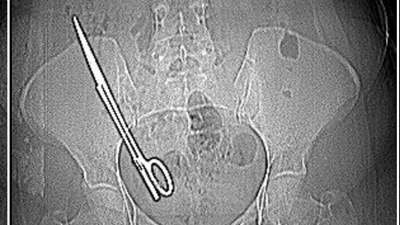

Ameliyatta karnında unutulan makas, 7 yıl sonra baş ağrısıyla ortaya çıktı

Kahramanmaraş'ta baş ağrısı şikayetiyle hastaneye giden Fatma Kala'nın (36) karnında 16 santimetre uzunluğunda ameliyat makası tespit edildi. 7 yıl önce geçirdiği kist ameliyatı sonrası karnında makas unutulduğu ortaya çıkan Kala, ameliyatı yapan doktor hakkında savcılığa suç duyurusunda bulunduğunu belirterek, "Hep haberlerde duyuyordum böyle olayları, ameliyatta sargı bezi, iğne aynı şeyin daha fazlası başıma geldi maalesef. Ben 7 yıl boyunca mucize eseri hayatta kalmışım" dedi

İddiaya göre; Koray Ş., 7 yıl önceki ameliyattan dolayı bir komplikasyon oluştuğunu ve acilen ameliyat etmesi gerektiğini söyledi. Doktorun tavırlarından şüphelenen Fatma Kala, ameliyat olmayı reddedip KSÜ Sağlık Uygulama ve Araştırma Hastanesi'ne gitti. Burada yapılan tetkiklerde Kala’nın karnında 16 santimetre uzunluğunda makas olduğu tespit edildi. Ameliyatla karnındaki makas çıkarılıp sağlığına kavuşan Fatma Kala, hastaneden çıktıktan sonra avukatı aracılığıyla 7 yıl önce ameliyatı gerçekleştiren doktor Koray Ş. hakkında Kahramanmaraş Cumhuriyet Başsavcılığı’na suç duyurusunda bulundu.

Baş ağrısı şikayetiyle gittiği hastanede doktorların 'Karnında makas var' deyince şoke olduğunu belirten Fatma Kala, 2017 yılında kist ameliyatı olduktan sonra iç kanama geçirdiğini ve tekrar ameliyata alındığını, makasın da o ameliyatta unutulduğunu söyledi. Karnında makas varken küçük çocuğu ile birçok defa MR odasına girdiğini belirten Kala, “Bundan 7 yıl önce özel bir hastanede ameliyat oldum. O günün gecesinde tekrar iç kanama geçiriyorum ve ikinci ameliyatımı oluyorum. Bu ameliyatta maalesef ameliyat olan bölgemde ameliyat makası unutuyorlar ve biz bunu 7 sonra öğreniyoruz. Baş ağrısından dolayı hastaneye gittik. Hastanede doktorumuz MR'a girmem gerektiğini söyledi. Ben MR teknisyenine daha önce çocukla beraber MR odasına girdiğimde benim sağ tarafımda çekme olduğunu söyledim.

Teknisyen bana 'Bu şekilde seni MR'a alamam, çok tehlikeli. Acilen ameliyat olduğun doktoru bul' dedi. Doktorumuz bizi hemen röntgene aldı. Röntgende bir yabancı cisim görmüş ama bize söylemedi, ‘Daha önceki ameliyatından dolayı bir komplikasyon oluşmuş. Seni ameliyat edip dedi o komplikasyonu ortadan kaldırmam gerekiyor’ dedi. Biz doktorun telaşlı tavrından şüphelendik. Eşimle birlikte tıp fakültesine gittik. Oradaki acil doktorlarına başımızdan geçen olayı anlattık. Onlar beni röntgene soktu. Oradan ilaçlı tomografiye girince daha önceki ameliyatımda bırakılan makas orada görüldü. Genel cerrahi bölümünde bu makas çıkarıldı'' diye konuştu.